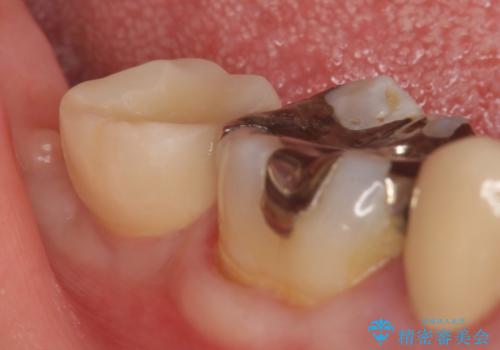

- 右下7番にインプラント治療を行った症例です。

CT撮影を行い状態を確認後、インプラント(ストローマン)の埋入(一次手術)を行いました。

インプラントと骨の定着を待った後に二次手術を行い、カスタムアバットメント、オールセラミッククラウンによる補綴を行いました。